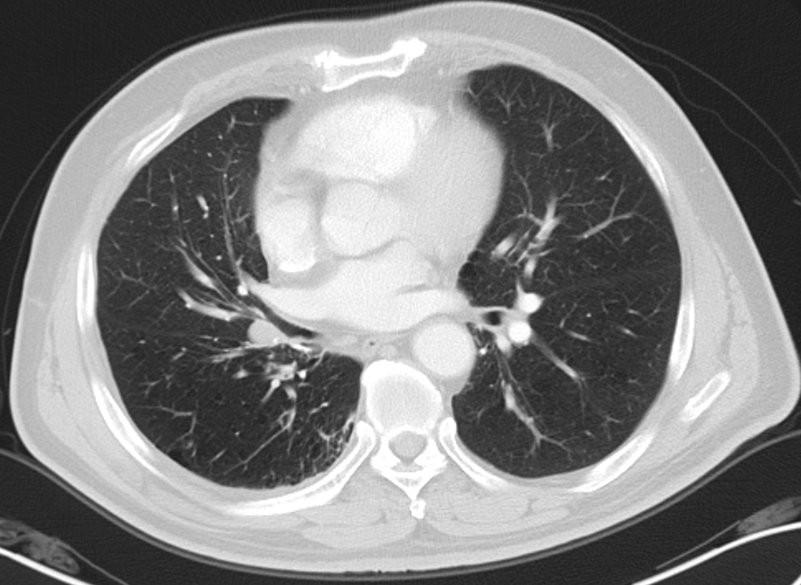

2018-3-30日入院患者入院后完善检查,行E-BUS检查,病理提示腺癌,基因检测提示L858R突变。诊断为,右肺中叶腺癌r T1bN1M0-IIB期,右肺下叶浸润性腺癌p T2aN0M0-IB期,VATS右肺下叶切除术后,患者家属考虑到既往已行右肺下叶切除术,且高龄,担心再次手术患者不能耐受,拒绝手术治疗。患者于2018-4-1日起行右肺腺癌术后肺门复发灶局部放疗,放疗计划剂量DT:60Gy/30Fx,同时行AC方案同步化疗,具体用药:培美曲赛0.98g ivgtt d1 +卡铂540mg ivgtt d1,q3w,放疗期间出现III度白细胞减少及II度血小板减少,予以升白细胞治疗及血小板治疗后好转,末次放疗时间为2018-5-16日。2018-6-15日及2018年7月18日行AC-T3-4周期化疗,术后予以定期随访。

(2018年5月20日胸部CT)